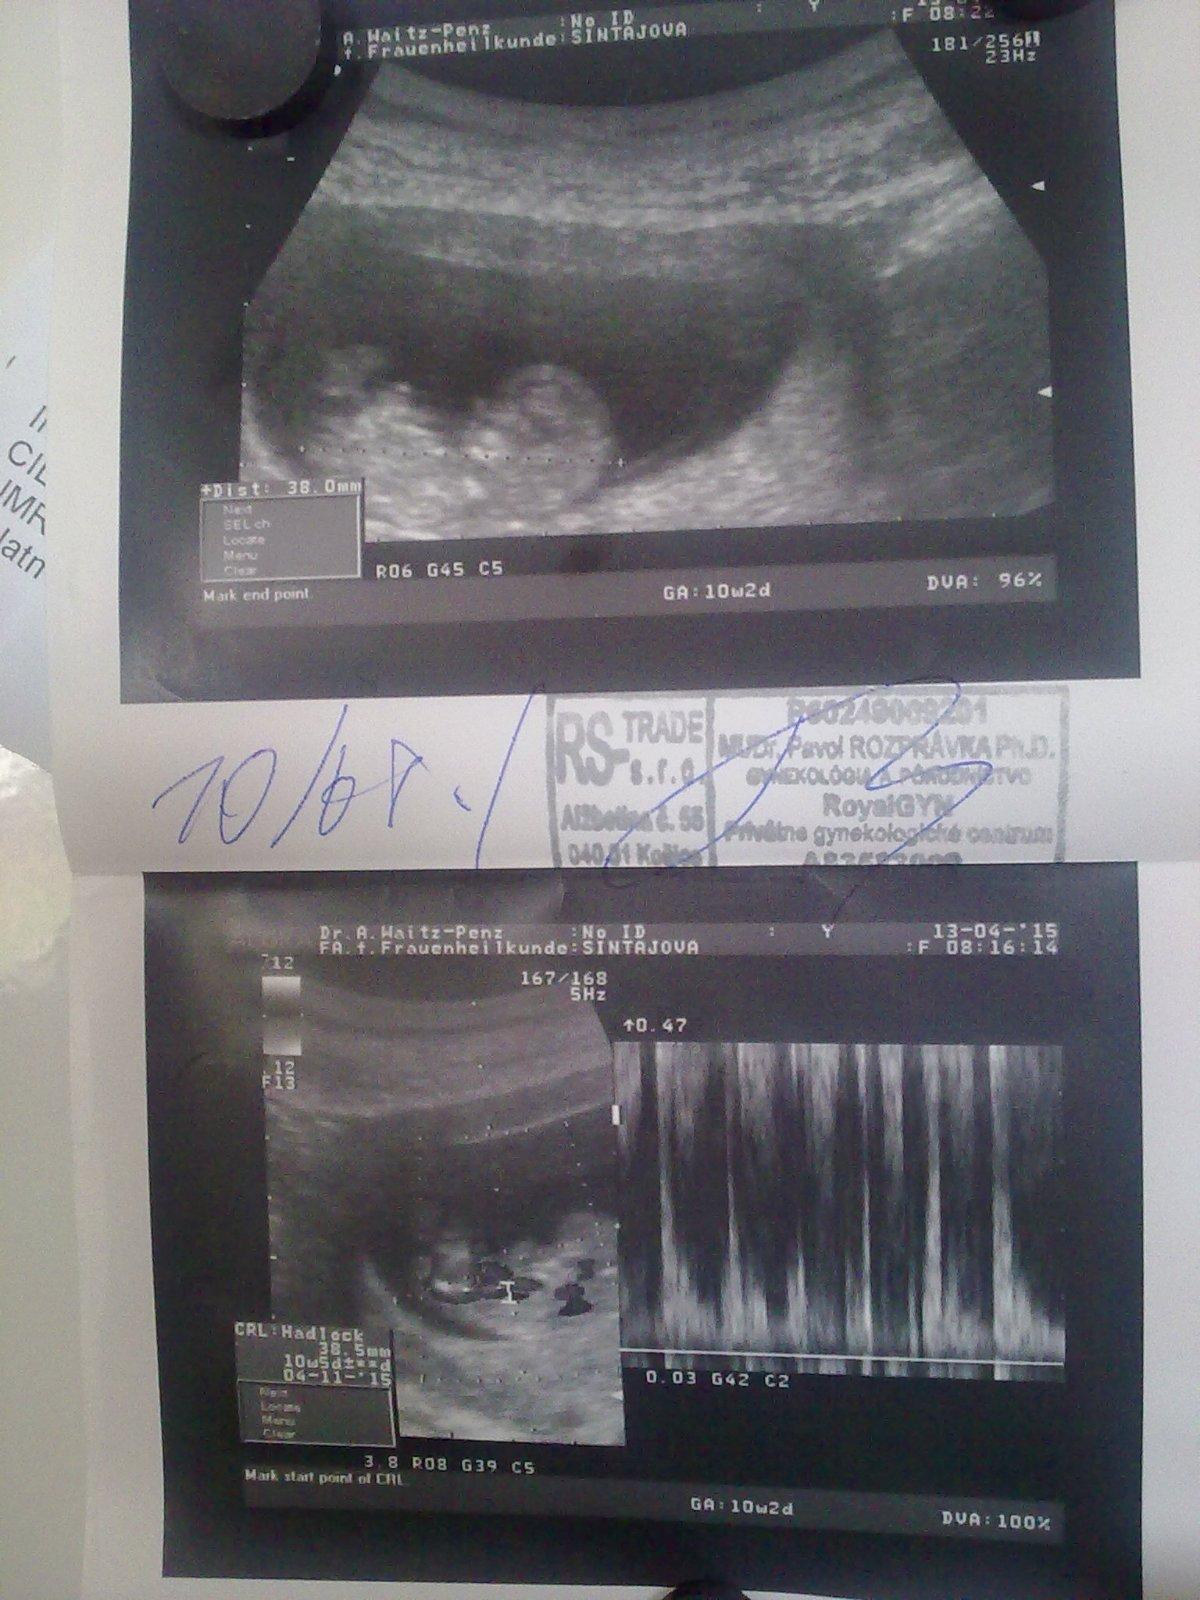

tak uz mame aj foto a frekvenciu srdiecka🙂